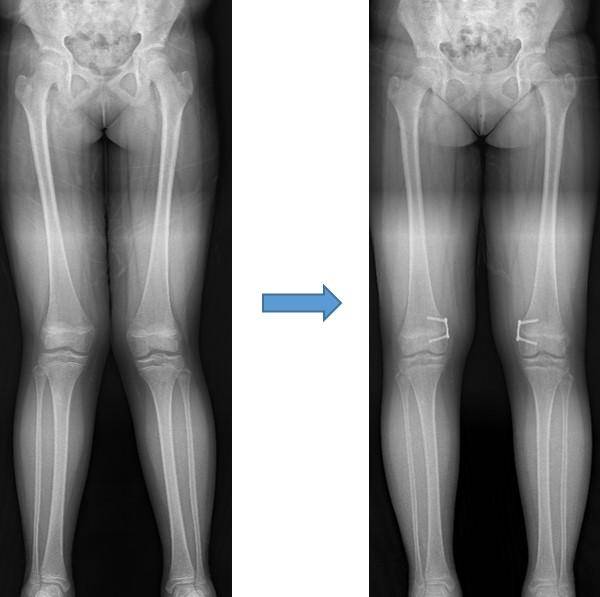

# 수진(가명·여·10세)양의 어머니는 아이의 다리가 살짝 휘어 보여 걱정이었다. 양쪽 무릎이 아프다며 한동안 밤잠도 설치는 아이를 보니 걱정은 더욱 커졌다. 결국 아이와 함께 병원을 찾았다. 엑스레이 검사 결과 X자형으로 다리가 휜 외반슬을 진단받았고, 교정을 위해 반성장판 유합술을 받았다. 수술 후 1년이 지난 지금 수진 양의 다리 변형은 완전히 교정됐고 무릎 통증도 사라졌다.

수술 방법으로는 ‘교정 절골술’이나 ‘반성장판 유합술’이 있는데, 이 중 반성장판 유합술은 일시적으로 한쪽 성장판의 기능을 억제해 아이가 성장하면서 변형이 교정될 수 있도록 하는 수술법입니다.

최근에는 ‘8’자 모양의 금속판을 이용한 ‘반성장판 유합술’이 시행되고 있습니다. 이 방법은 교정이 완료돼 금속판을 제거하면 성장이 재개되기 때문에 상대적으로 더 어린 나이에 시행이 가능합니다.

수술시기를 비교적 편하게 잡을 수 있고, 효과적인 교정을 얻을 수 있다는 것이 장점입니다. 또한 입원기간이 평균 하루 정도로 짧고 회복이 빨라 대부분의 경우 바로 활동이 가능합니다.

하지만 성장이 거의 끝나가거나 성장이 종료된 후에는 반성장판 유합술로는 교정을 얻을 수 없어 ‘교정 절골술’을 시행해야 합니다.

교정 절골술은 무릎 주위의 허벅지뼈 또는 정강이뼈를 절골한 후, 휘어진 뼈를 금속판으로 고정해 균형을 맞추는 원리로 이뤄지는 수술입니다.